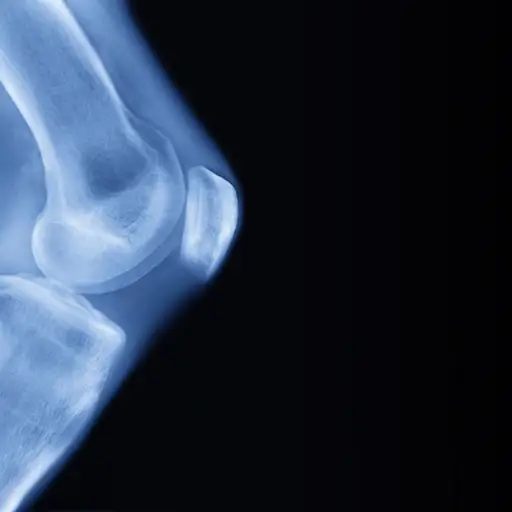

x光帮助诊断骨关节炎

金医生说,你的病史、体格检查和x光检查将有助于诊断关节炎。在检查过程中,医生会观察你的关节并移动它们,以测试什么动作会引起疼痛。(金医生说,如果压迫关节的运动引起疼痛,很可能是骨关节炎。)x射线图像可以显示骨骼之间的空间是否变窄——这是软骨丧失的迹象。金姆博士说,核磁共振通常不需要,但可以提供更详细的肌腱及其周围组织的图像——如果你的医生想要寻找退化的早期迹象,这是很有用的。